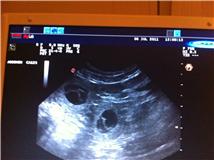

Bilder fra Ultralyd 6/7-2011:

I dette bilde ser du tre.

Det ene oppe til høyre er vanskelig å se.

Dette er en noe usikker metode for å vite hvor mange valper det er, men vet i hvertfall at hun er drektig. Vi kunne telle fem valper, men det er veldig usikkert. Det kan være flere eller færre. Tiden vil vise.